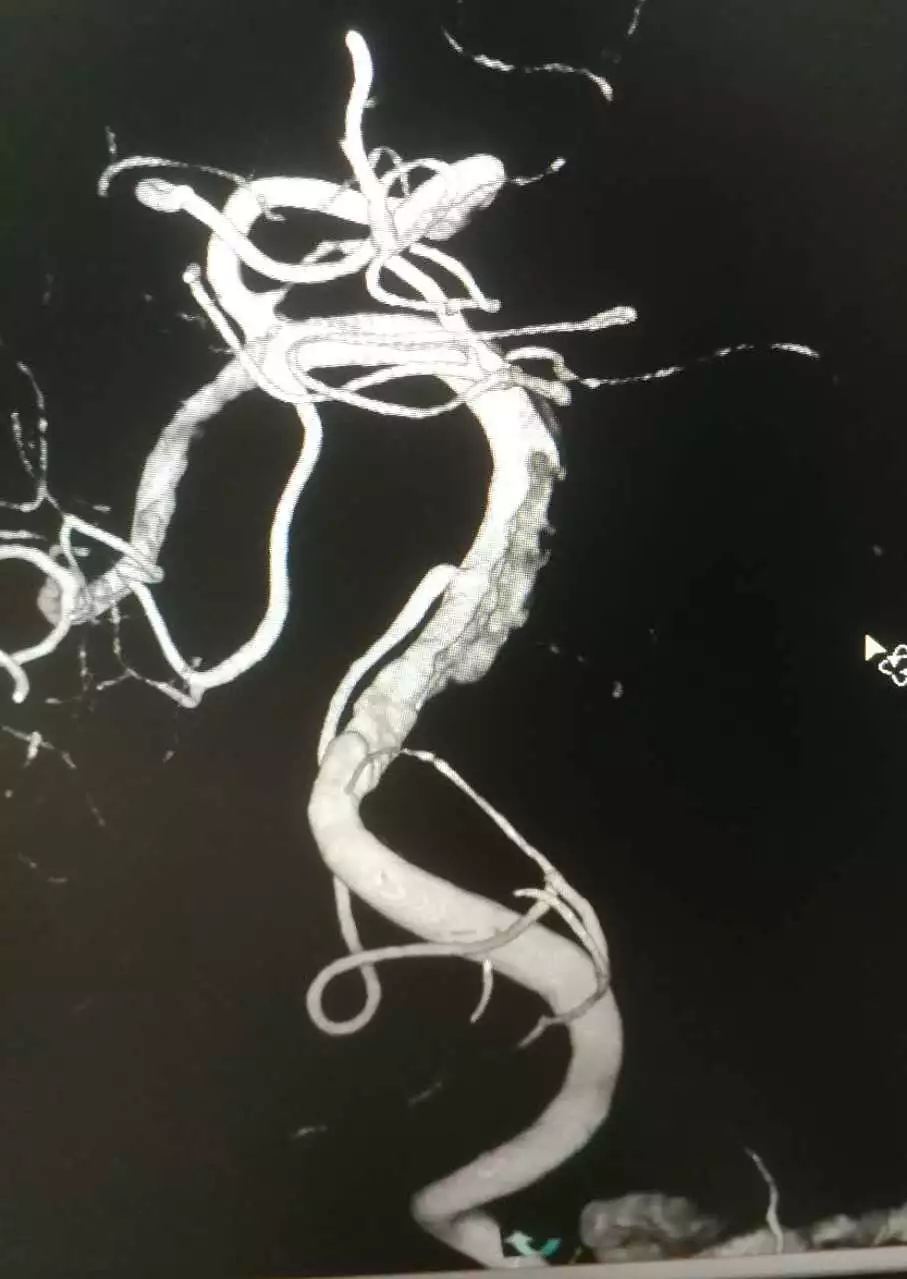

术中脑血管造影显示病灶部位

当造影剂充盈脑血管后,发现病人左侧椎动脉V4段血管病变,刘忠锦副主任当即给予动脉溶栓药物,进行桥接治疗。病人术后意识明显改善,言语不清迅速缓解,肢体活动良好,复查头CT无出血,安返病房。